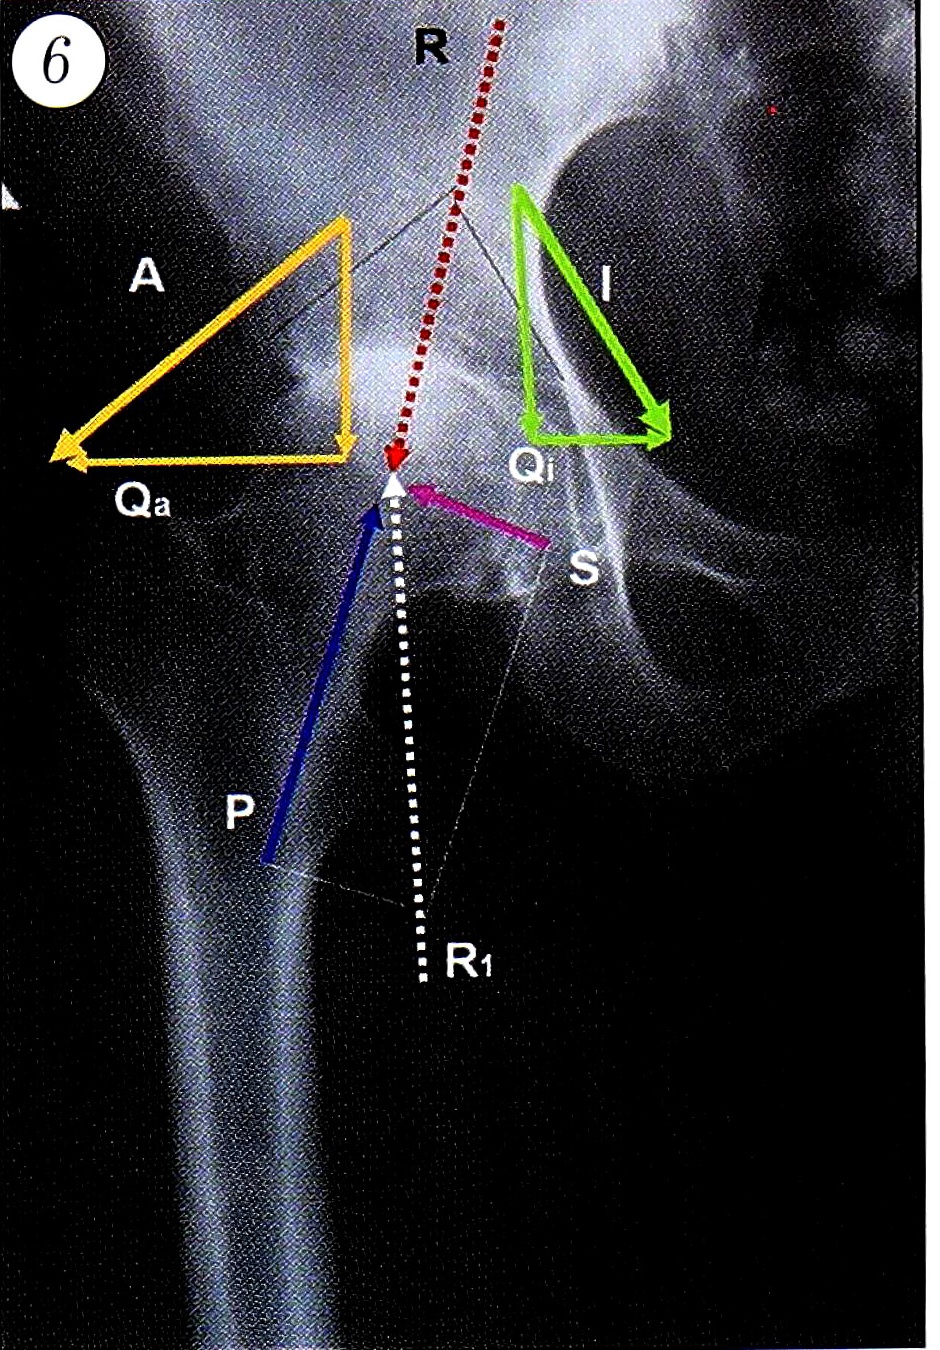

Данная ситуация усугубляется тем, что в момент опоры срезающий компонент вектора силы реакции опоры (S) еще больше нарушит баланс сил, стремясь также вывихнуть головку бедренной кости из вертлужной впадины. Суммарное значение горизонтальной составляющей вектора силы ягодичных мышц и срезающего компонента силы реакции опоры превысит суммарное значение вектора силы подвздошной мышцы и давящего компонента силы реакции опоры. И чем больше будет медиальное отклонение сурсила, тем большим окажется сдвиг баланса сил в области тазобедренного сустава в сторону вывихивания головки бедренной кости (рис. 6). В клиническом плане можно говорить о тенденции к выдавливанию головки из вертлужной впадины при стоянии и ходьбе; к тому же при каждом моменте опоры действующие в этом направлении силы увеличиваются пропорционально весу тела. Иными словами, возникает тенденция к центробежному смещению головки бедренной кости.

Рис. 6. Распределение векторов сил при медиальном положении сурсила: баланс сил смещается в сторону отводящих мышц.